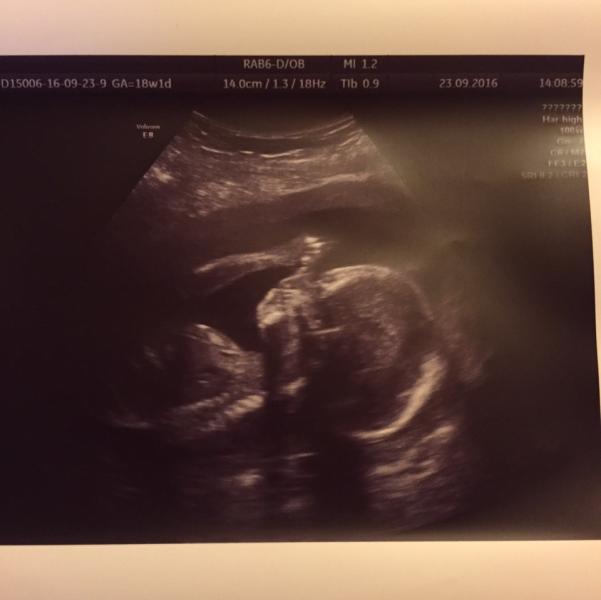

Вот и мы сходили на УЗИ к Мазырко на Арбат. Очень остались довольны. Правда пока ждали, нервишки шалили, притом что перед нами вышла пара в слезах. Меня это впечатлило. Итог: наш пупсик соответствует сроку 18 недель и 5 дней, предполагаемая масса 250 гр))), чсс 148 ударов, лежит вниз головой, степень зрелости плаценты 0, длина шейки 42 мм, и на десерт: у нас будет парень)))💪🏽👼🏻. Восторгу папы не было предела. Узист она замечательный, очень добродушная, внимательная, все рассказала, показала. Мы в восторге. При том что нам дали диск и фоточки).